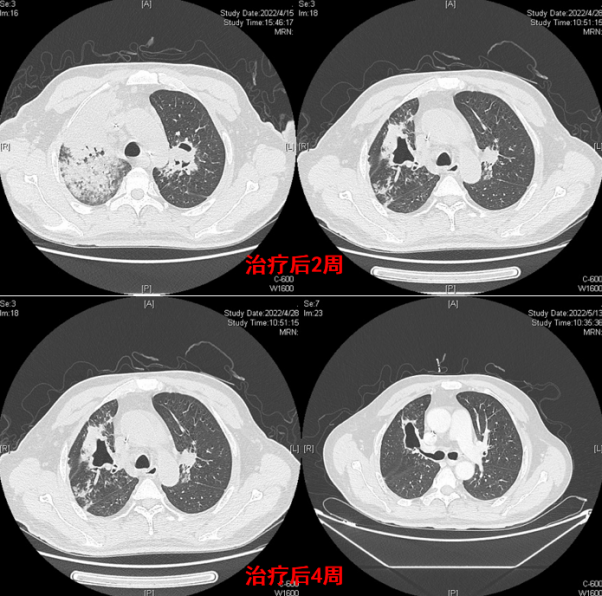

病例1:女性,22岁,既往有1型糖尿病病史,在感染新冠病毒后合并毛霉(米根霉)感染。影像学检查显示双肺存在磨玻璃影,且在此基础上迅速出现实变、空洞及坏死等病变,病情进展极为迅猛(图1)。该患者于2022年底(新冠疫情优化管控后疫情较为严峻时期)从内蒙古前往北京就医,进入急诊室当天便因呼吸衰竭不幸死亡。此病例凸显COVID-19合并毛霉感染的严重性,尤其是对于存在基础疾病(如糖尿病)的患者,病情可快速恶化,致死性极高,也反映出在疫情特殊时期,此类重症感染患者救治面临的严峻挑战。

图片

1  病例1影像学表现